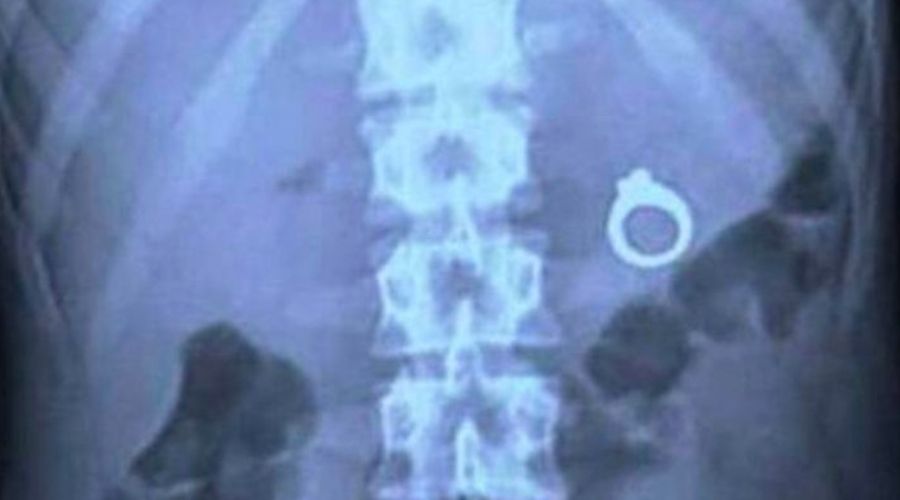

The Love Inside

This is a disaster. A complete disaster. The reason this went wrong is because someone decided to put an engagement ring in a milkshake, and their partner unknowingly swallowed it. This should be at the top of your list of “what not to do” when proposing, because you definitely shouldn’t be sending someone to the hospital with your romantic gesture.

The thought behind it is sweet, but the execution falls short. They should have gone for a Bloody Mary instead, placing the ring on top of the absurdly large food stack on the straw. No proposal should come with the risk of choking.